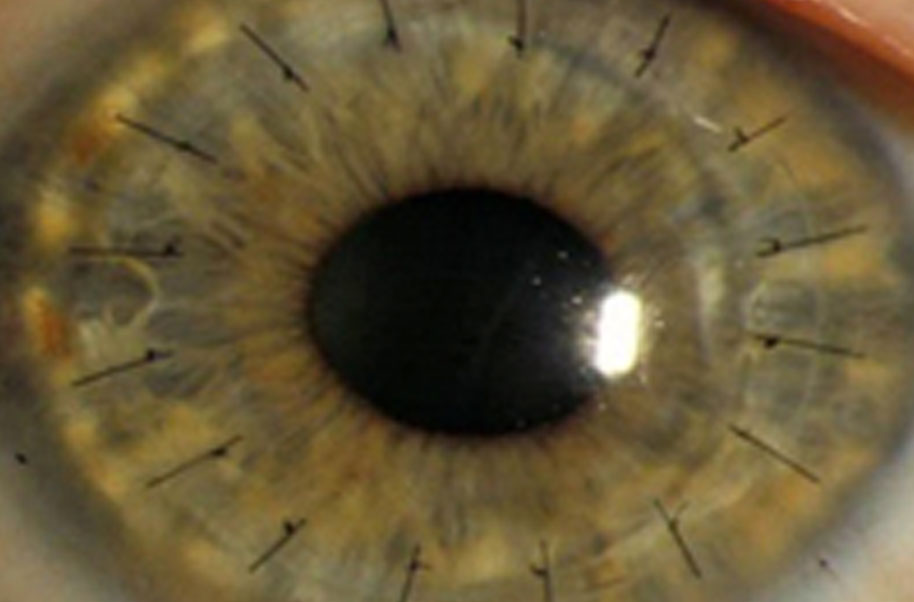

The cornea is the clear, protective outer layer of the eye. ... If the cornea becomes damaged through disease, infection, or injury, the resulting scars or discoloration can interfere with vision by blocking or distorting light as it enters the eye.

Keratitis is an inflammation of the cornea. Noninfectious keratitis can be caused by a minor injury, or from wearing contact lenses too long. Infection is the most commoncause of keratitis. Infectious keratitis can be caused by bacteria, viruses, fungi or parasites.